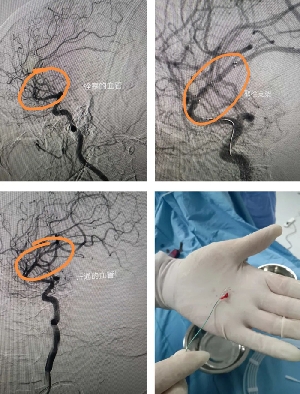

患者突發(fā)卒中,神經(jīng)介入緊急取栓救命!

患者老年女性,既往有先心病史,因心衰收住院。6月29日突發(fā)左側(cè)肢體偏癱,腦CT未見(jiàn)出血,診斷急性腦梗死。值班醫(yī)生立即聯(lián)系神經(jīng)內(nèi)三科副主任馬磊!馬主任認(rèn)為患者為心源性栓塞,立刻啟動(dòng)應(yīng)急預(yù)案,建議緊急取栓!家屬簽字同意后,立刻將患者轉(zhuǎn)運(yùn)到介入室。造影提示患者為右側(cè)大腦中上干閉塞,大腦中動(dòng)脈m2段閉塞,取栓困難,